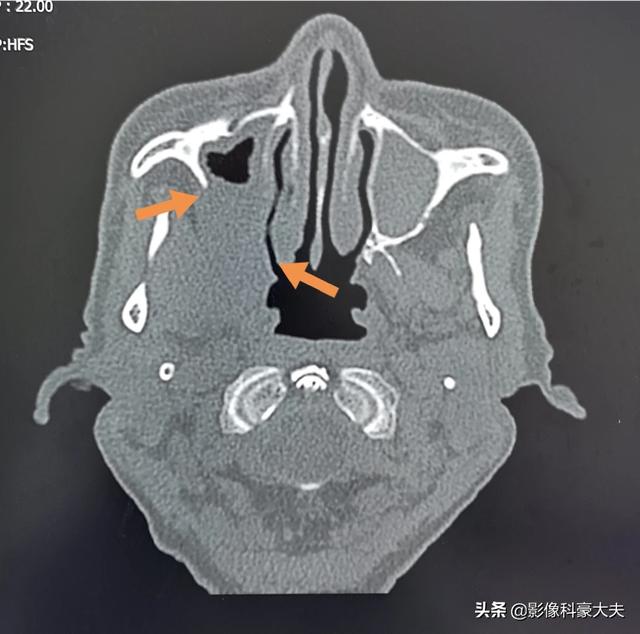

この老人は、右側の歯痛と頬の膀胱の痛みで、2ヶ月以上、歯の根の炎症がある老人のように薬を服用してきたが、現在では上顎洞癌における骨破壊上へ